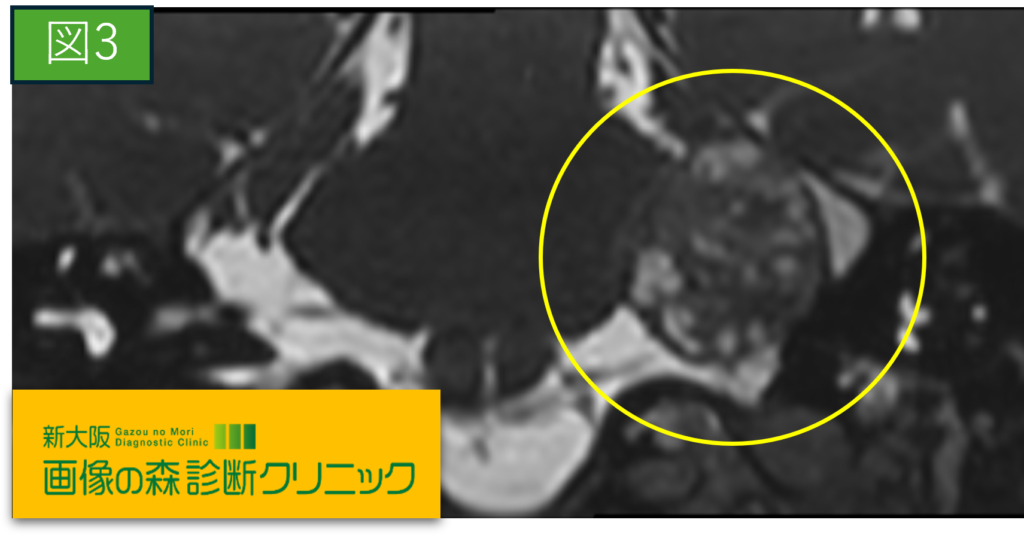

症例画像から図1~図4は聴神経腫瘍の画像です。

〇内に聴神経腫瘍を示します。

聴神経腫瘍とは、内耳から脳に渡る内耳神経に発生する良性腫瘍です。画像に示すように腫瘍が大きくなると神経を圧迫し症状が生じます。